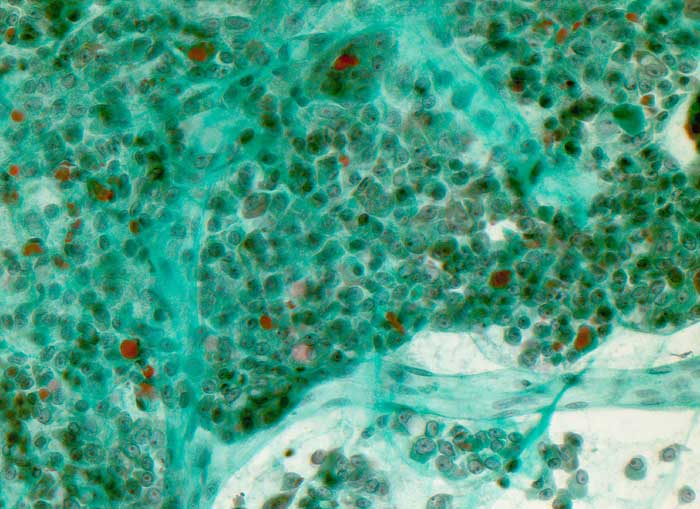

Ausgeprägte Kernpolymorphie, Nukleolenatypie und unscharfe Zytoplasmagrenzen der oxyphilen Zellen sind Malignitätszeichen. Eine Unterscheidung von onkozytären Adenomen und Karzinomen ist zytologisch aber nicht sicher möglich.

Gezeigt werden zwei Fälle von histologisch gesicherten onkozytären Karzinomen.